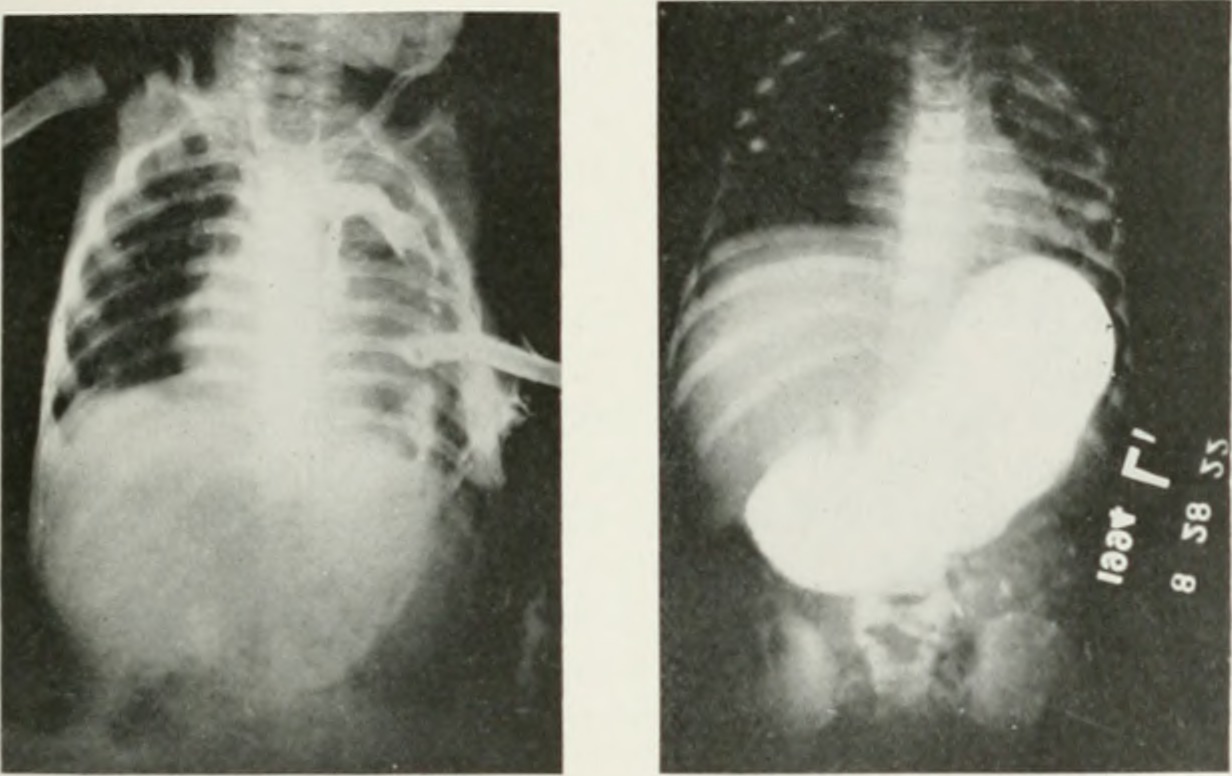

E mphysema is a progressive respiratory condition that causes the tiny air sacks in the lungs to burst. As this damage takes place, the lungs lose their ability to remain elastic. The lungs progressively lose their ability to absorb Oxygen and release carbon dioxide as well, which can easily lead to sudden death. Fortunately, emphysema treatment can prevent the condition from getting worse and relief the symptoms. Causes of Emphysema People who have had other lung or heart conditions are at a greater risk of developing emphysema. But the risk also increases if the individual has exposure to tobacco or cannabis smoke. Other risk factors are exposure to dust, smoke in the workplace, and air pollution. Emphysema Treatment The first treatment of emphysema is medication. Medicines reduce swelling and inflammation in the lungs. They also open the airways and prevent further infections. Typically, people use short-acting medications to lessen pain promptly and long-acting drugs to prevent or control the symptoms. The next treatment mode is pulmonary rehabilitation. This program is effective at managing symptoms and enhancing the quality of life. In some cases, it includes nutritional counseling and exercise. Oxygen supplementation is another emphysema management option that may help patients with severe COPD. As the condition progresses, the patient requires a higher amount of Oxygen. This option will help a patient breath with considerable ease and remain alert always. Health professionals sometimes recommend lung reduction surgery. Surgery is used when all the other emphysema management options have proven unhelpful. The aim of this operation is to remove part of the damaged lung, and if necessary, a lung transplant follows. Conclusion Every person has the right to help plan their healthcare. So, whenever a person notices any problems in the chest area or breathing difficulties, he or she should consult a doctor. The physical can put the person under emphysema treatment in time if the expert proves the individual is developing emphysema. [Photo: flickr.com]